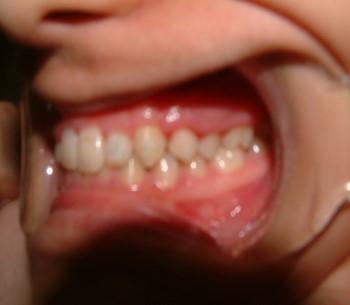

028 Δεύτερη περίπτωση Αρχική κατάσταση Η σημασία της στοματικής υγιεινής και ορθοδοντικής πρόληψης

Μετά το πέρας της ορθοδοντικής θεραπείας.